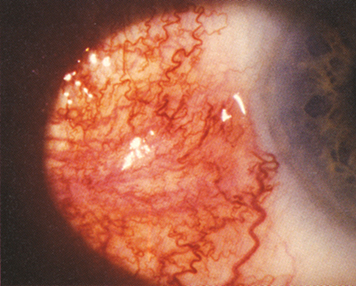

2. Nodular anterior scleritis: Immovable inflamed nodule(s) (see Figure 5.7.1).

Figure 5.7.1: Nodular scleritis.

Rapuano9781975243722-ch005_f015.jpg